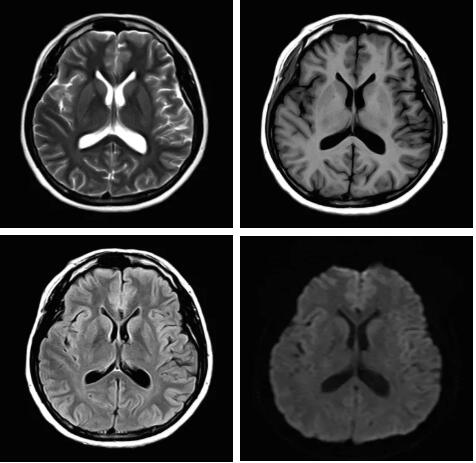

3.Pure射頻成像鏈

從成像源頭的磁體采用鍍膜新磁體高密度薄層鍍膜貼合技術(shù),獲得更好的磁場均勻度,奠定磁共振成像基礎(chǔ);采用3D RSCE微雕梯度精準(zhǔn)控制頻率和相位,輸出理想波形,實現(xiàn)渦流的“0”殘余,還原最真實的圖像信息;射頻接收端通過計算機(jī)人工智能對信號抗干擾處理,把信號放大并去除梯度、磁場等對信號干擾,再經(jīng)過二次人工智能信號識別,去除噪聲污染獲得純凈的信號;通過Pure射頻成像鏈的優(yōu)化和改進(jìn)使信噪比提升40%,這是磁共振領(lǐng)域革命性的顛覆和改變。